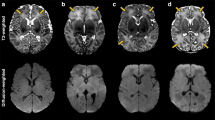

Results

An abnormal T2 signal intensity, with swelling of the MBs, was noted in 92 of the 231 infants (41%); abnormal MB signal was observed in 36% of the cases that had been originally reported as “normal” (Figs. 1 and 2; Table 1). When abnormal MB signal was present, the brain appeared otherwise normal in 50% of the cases. When additional abnormalities were noted, the near-total brain ischaemia pattern (24%) and predominant basal ganglia/thalamus pattern (17%) were the most common, followed by the predominant watershed pattern (9%). There was, however, a significantly greater percentage of cases with near-total brain ischaemia in the group with abnormal MB signal compared to the group with normal MB signal (24 vs 8%; p = 0.001; see Table 1). Consistent with this, the near-total group had the highest percentage of cases with MB injury (69%; see Table 1) reflecting the widespread injury observed in this subgroup.